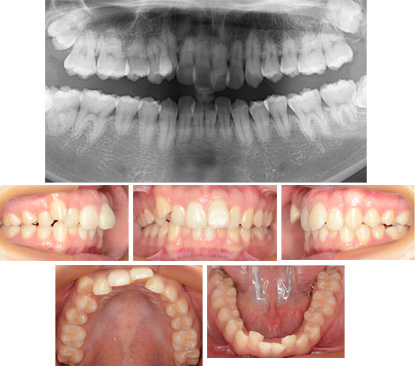

来院時の写真

気になっている点(主訴): 八重歯 乱杭歯

もう一つ大きな問題ありました。歯根が元々短い方です。治療を急がなければならない。歯の健康には注意して強い矯正力は加えられない。レントゲン写真を見て、この状態なら歯根吸収は進行しないと判断しました。この判断は私の治療経験が来るものです。

上には治療後のレントゲン写真をお見せしました。歯根吸収の進行はありませんでした。初診時と同じです。しかし、歯根が短い事には変わりがありません。これには今後とも注意が必要です。

前歯部叢生と上顎前突がありました。そこで上顎第一小臼歯を抜歯してリンガルブラケットで治療をおこないました。全体の歯根が短い。

抜歯部位 : 上顎第一小臼歯

もともと全体の歯根が短かかったです。進行しないように注意して弱い矯正力で治療しました。強い矯正力は歯根吸収を起こすというのにはエビデンスがあります。結果としては歯根の長さには変化はありませんでした。